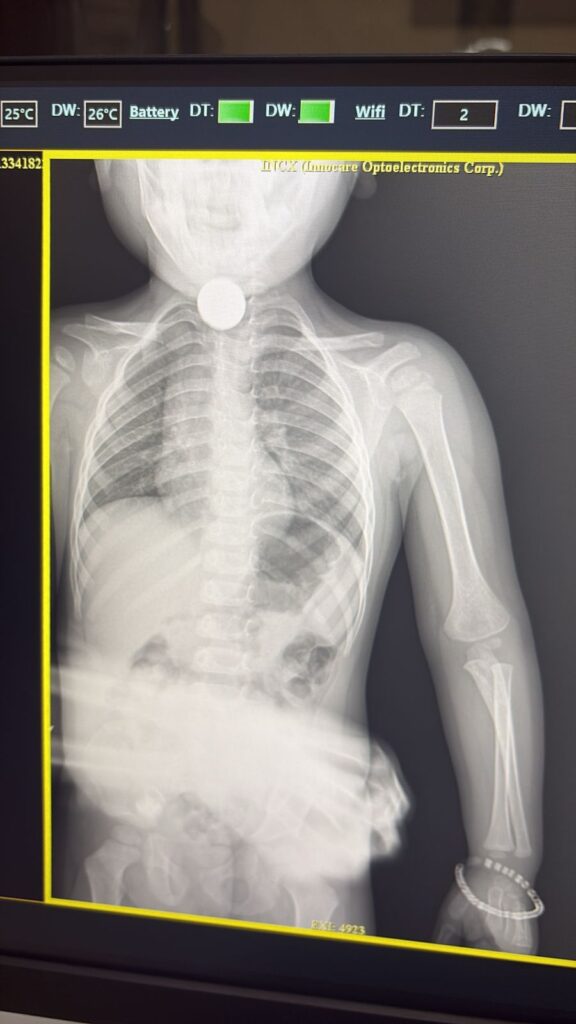

3 साल के बच्चे के गले में फंसा सिक्का डॉक्टर ने ऑपरेशन कर निकाल खेलते खेलते निकाल लिया था 5 का सिक्का

शाजापुर। के लक्ष्मी नगर में 3 साल के बच्चे ने खेलते खेलते ₹5 का सिक्का निकाल लिया बच्चे की तबीयत बिगड़ने पर परिजनों से तुरंत जिला अस्पताल ले जहां डॉक्टर ने जांच में पाय कि बच्चे के गले में सिक्का फंसे हुए हैं

जिला अस्पताल में के डॉक्टर तेजपाल सिंह जादौन ने बच्चों की जांच की उसका एक्सरे कराया जिसमें गले में सिक्का फंसे होने की पुष्टि हुई इसके बाद जादौन ने ऑपरेशन कर दूरबीन की मदद से पांच का सिक्का मुंह से बाहर निकाल दिया सिक्का निकलते ही बच्चे ने राहत की सांस ली परिजनों ने डॉक्टर का आभार व्यक्त किया बच्चों की हालत स्थिर है डॉक्टर ने परिजनों छोटे बच्चों को खेलते समय सावधानी बरतने की सलाह दी